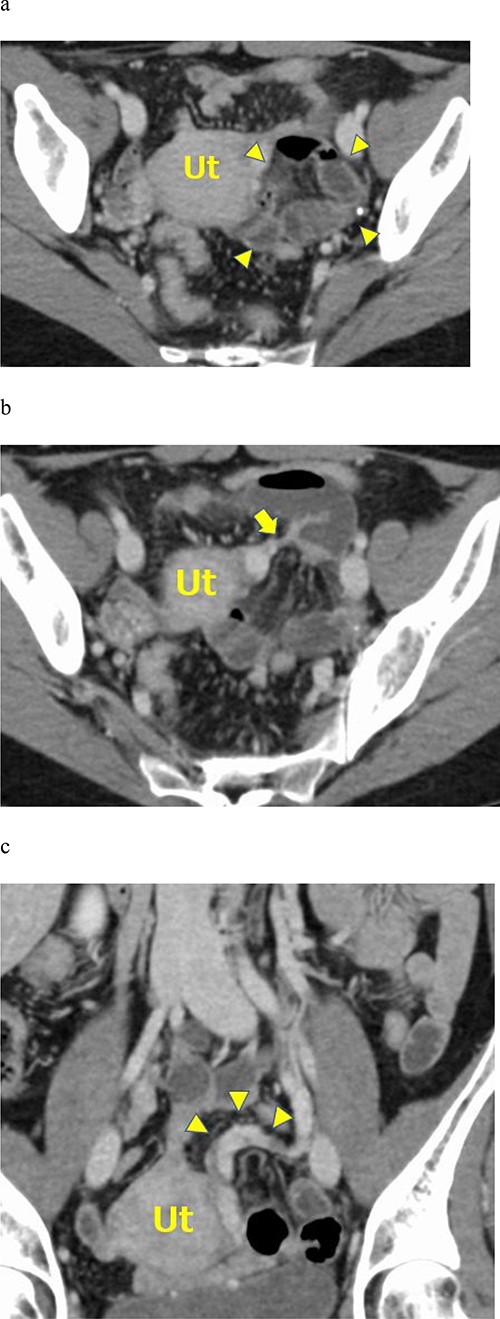

a. Contrast-enhanced axial CT showing fluid-filled dilated small bowel loops in the posterior pelvic cavity (arrowheads). The small bowel loops compressed the uterus on the right side. b. Contrast-enhanced axial CT showing mesenteric vessels converging around the uterus (arrow). c. Contrast-enhanced coronal CT images showing the left ovarian venous dilatation and tortuousness (arrowheads).

An abdominal X-ray examination revealed no niveau formation. Abdominal contrast-enhanced computed tomography (CT) using a 320-row multidetector CT (MDCT) scanner (Aquilion ONE, Canon, Japan) was performed. The contrast-enhanced abdominal CT showed a cluster of dilated small bowel loops on the left side of the pelvic cavity and bowel loops compressing the uterus on the right side of the pelvis (Fig. 1a). The CT scan showed mesenteric vessels converging around the uterus (Fig. 1b). A small amount of ascites was found at Douglas’ fossa. Contrast-enhanced coronal CT images showed left ovarian venous dilatation and tortuousness (Fig. 1c). Enhancement of the wall of the small bowel loops was not decreased, indicating the absence of bowel ischemia.

In our patient, MDCT images showed left ovarian venous tortuousness and dilatation. This may appear early by the small bowel loop compressing the round ligament, which has ovarian blood vessels. Tortuousness and dilation of the ovarian veins were noted in three cases, including ours [4]. This may be used as a new CT feature for early detection.